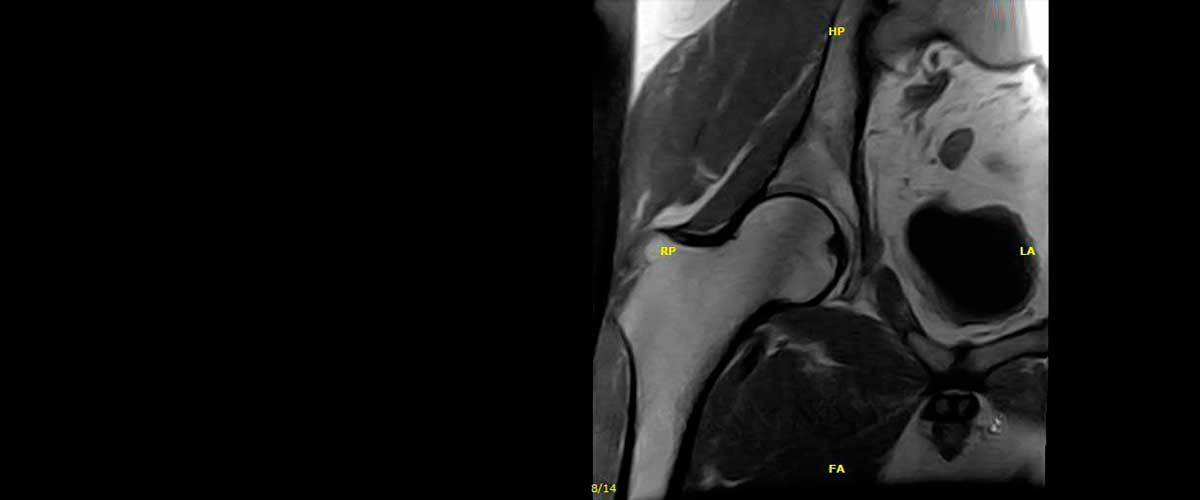

Contamos con equipos de resonancia magnética musculo-esquelética capaces de realizar exámenes con descarga de peso o bipedestación.

En nuestros centros se realizan estudios y diagnósticos de resonancia magnética musculo-esquelética

de Resonancia ,Magnética Musculo-Esquelética, de la marca italiana Esaote, es único en su diseño ya que nos permite realizar exámenes en bipedestación (el paciente estará de pie, para que se tenga otra perspectiva del comportamiento del cuerpo durante el examen).